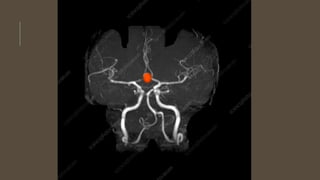

INVESTIGATIONS

• MRI and MRA

INVESTIGATIONS • CT scan •CT angiogram • MRI and MRA • DSA